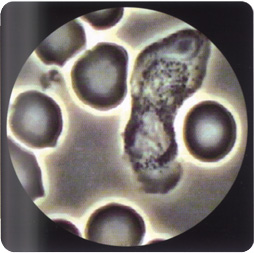

2.骨髓象 除原粒細胞比例增高外,嗜酸性粒細胞明顯增多並有左移根據細胞形態可分為三型:①原粒細胞型:血象和骨髓均有原粒細胞增多。②幼稚細胞型:除骨髓幼稚嗜酸性粒細胞明顯增多外,外周血中亦可見到此類細胞。③成熟細胞型:以成熟嗜酸性粒細胞增多為主,包括嗜酸性中、晚幼粒細胞增多,原粒細胞正常或稍增多。